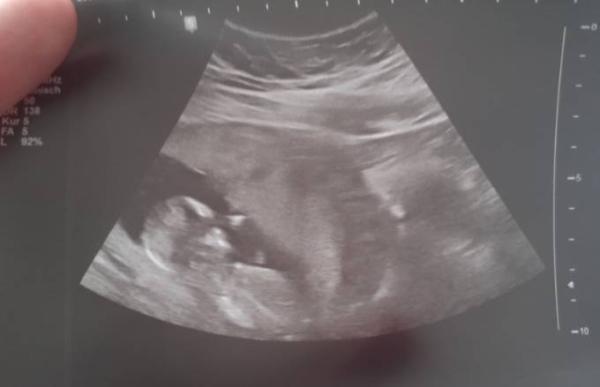

Hallo meine lieben Ich bin seid gestern in der 14.ssw und kann es immer noch nicht glauben trotz dieser übelkeit und denn ganzen Symptomen Ich hab 2018 meine Pille abgesetzt und erst 2022 kommt diese Überraschung aber ich realisiere bis jz nicht das ich wirklich ein menschen im Bauch habe der sich langsam entwickelt ich sehe diese ultraschall bilder und manchmal muss ich einfach drauf los weinen ich verstehe nicht wieso ich es nicht glauben kann Ab wann habt ihr realisiert das ihr schwanger seid und das da wirklich ein kleiner Mensch in euch ist? LG. Sophie Im Bild sieht man ein ultraschall bild von Freitag, 24.06.

Bild zu Realisieren das man schwanger ist - Schwanger - wer noch? Rund um die Schwangerschaft